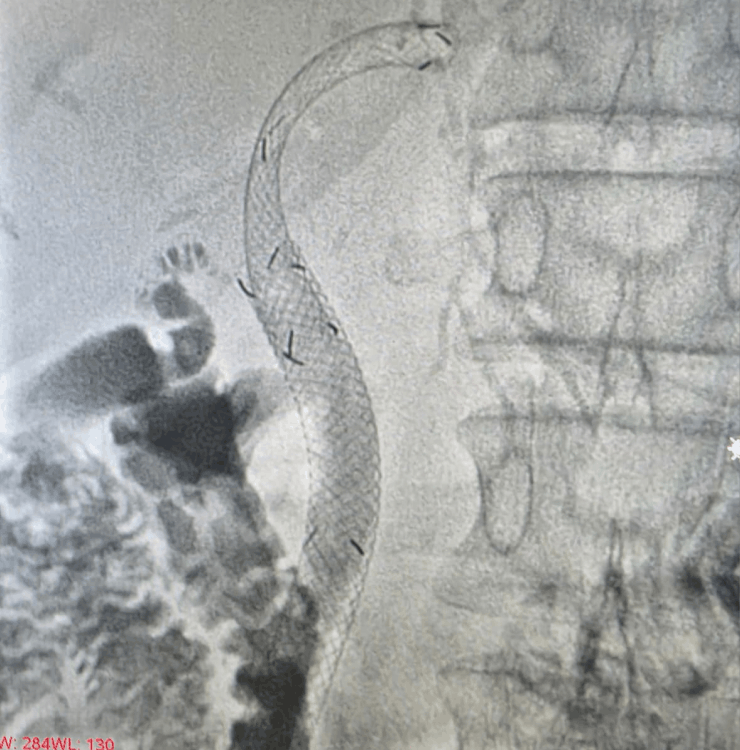

- Definitive stenting across the blockage using plastic or metal stents to restore long‑term bile flow.

Biliary stenting

- Regular follow‑up imaging to ensure the stent or catheter is functioning well

3.How long will the stent or drain stay in place?

This depends on the underlying disease. In many malignant obstructions, metal stents are intended for long‑term use. External drains may be capped or removed once internal drainage is adequate and bilirubin levels have improved.